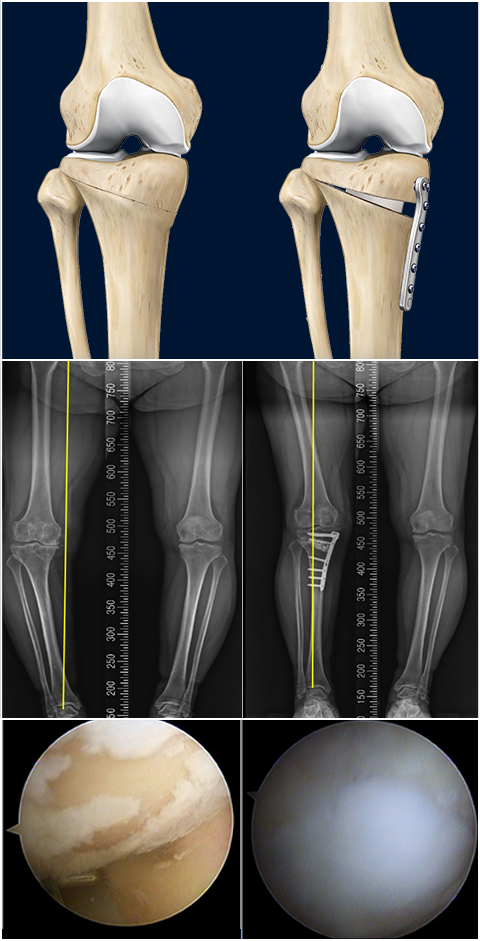

근위경골절골술은 오다리 변형으로 인해 무릎 안쪽 관절에 집중되는 체중 부하를 교정하기 위한 수술입니다.

무릎 아래 뼈인 경골의 정렬축을 조정하여, 이를 통해 무릎 안쪽 연골에 집중되던 부담을 줄이고 통증 완화를 기대할 수 있습니다.

여기에 연골의 근본적인 재생을 유도하는 줄기세포(카티스템) 연골재생술을 결합한다면 무릎 관절의 수명을 늘리는데 더욱 도움이 됩니다. 결과가 좋은

환자분의 경우에는 평생 무릎 인공관절을 안하는 경우도 있을 정도로 예후가 우수한 치료법입니다.